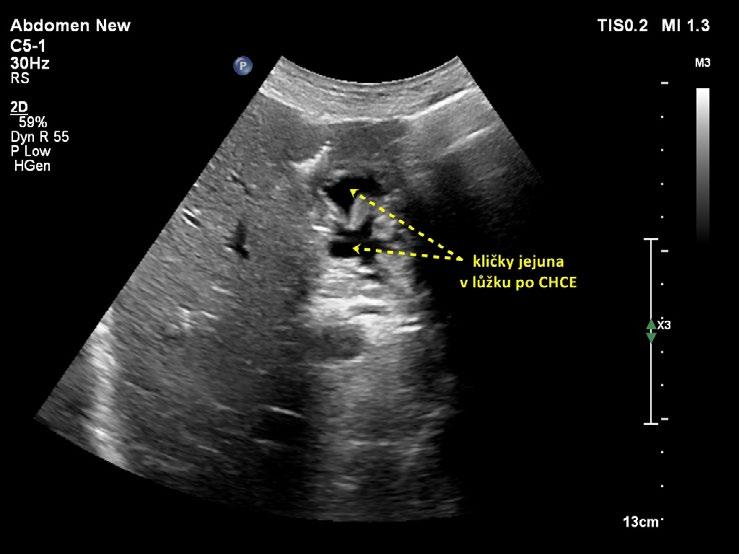

U jedinců po cholecystektomii se může do lůžka žlučníku vsunout bulbus duodena, většinou naplněný plynem, někdy tekutinou. Peristaltické pohyby ozřejmí, že jde o bulbus duodena, a nikoliv o patologický útvar. U pacientů po cholecystektomii spojené s Whippleovou operací (proximální pankreatoduodenektomie s resekcí distální třetiny žaludku) často v lůžku žlučníku zobrazíme kličky tenkého střeva (obr. 1.20).